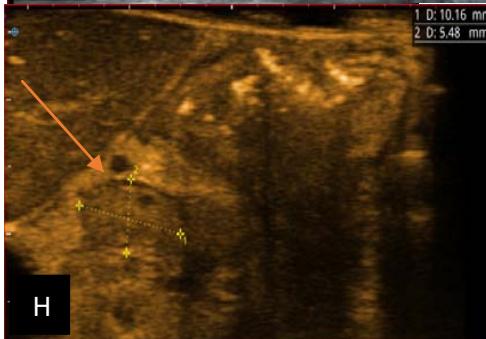

Figure 5: Abdominopelvic ultrasound control after 6 courses of chemotherapy in the same 3 year old patient with a ruptured left renal nephroblastoma; Images A, F, G, and H: show regression of the solid, endo and exo renal, left nephroblastoma mass treated with 6 courses of chemotherapy (current volume 430 ml vs) Images: B, C, and: show persistence of thrombotic permeation pan vena cava and ipsilateral renal. Image E: shows a volumetric regression of the intra-lesional hematic collection, at the tumor rupture estimated at 34.49 ml VS, Image I: represents the right kidney in B mode which is of normal echoculture. Source: Dr. Frederick Tshibasu Tshienda database.